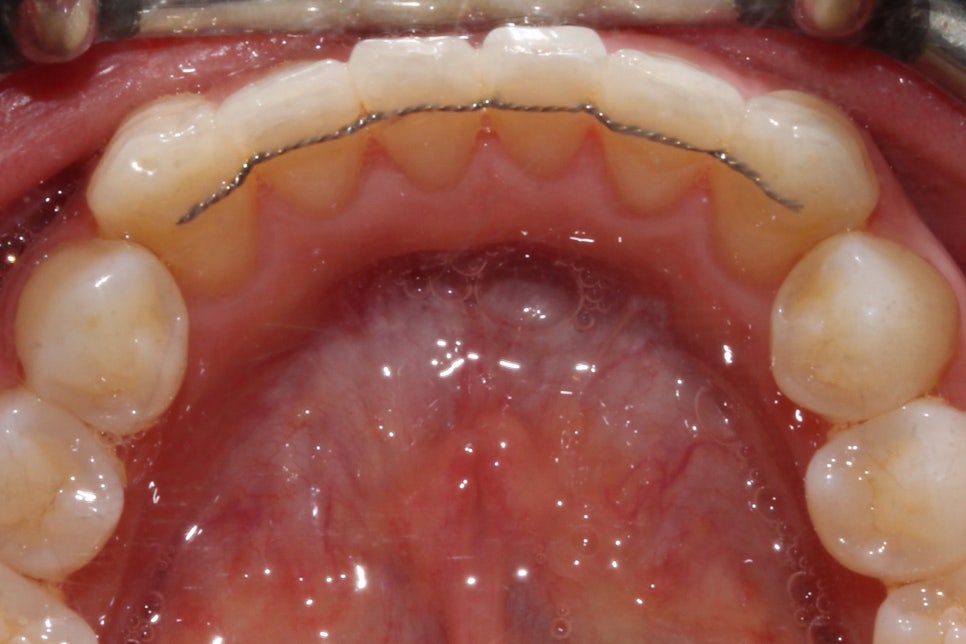

신논현역치과 교정 후 상하악의 교합면을 보시면

상악 중절치의 뻐드러짐 증상이 확연하게

사라진 것을 확인할 수 있는데요,

하악의 경우 교정 전 전치부의

삐뚤거림이 심했던 모습에서 교정 후

안모의 형태가 U자에 가까운 모습으로

교정된 것을 확인할 수 있습니다.